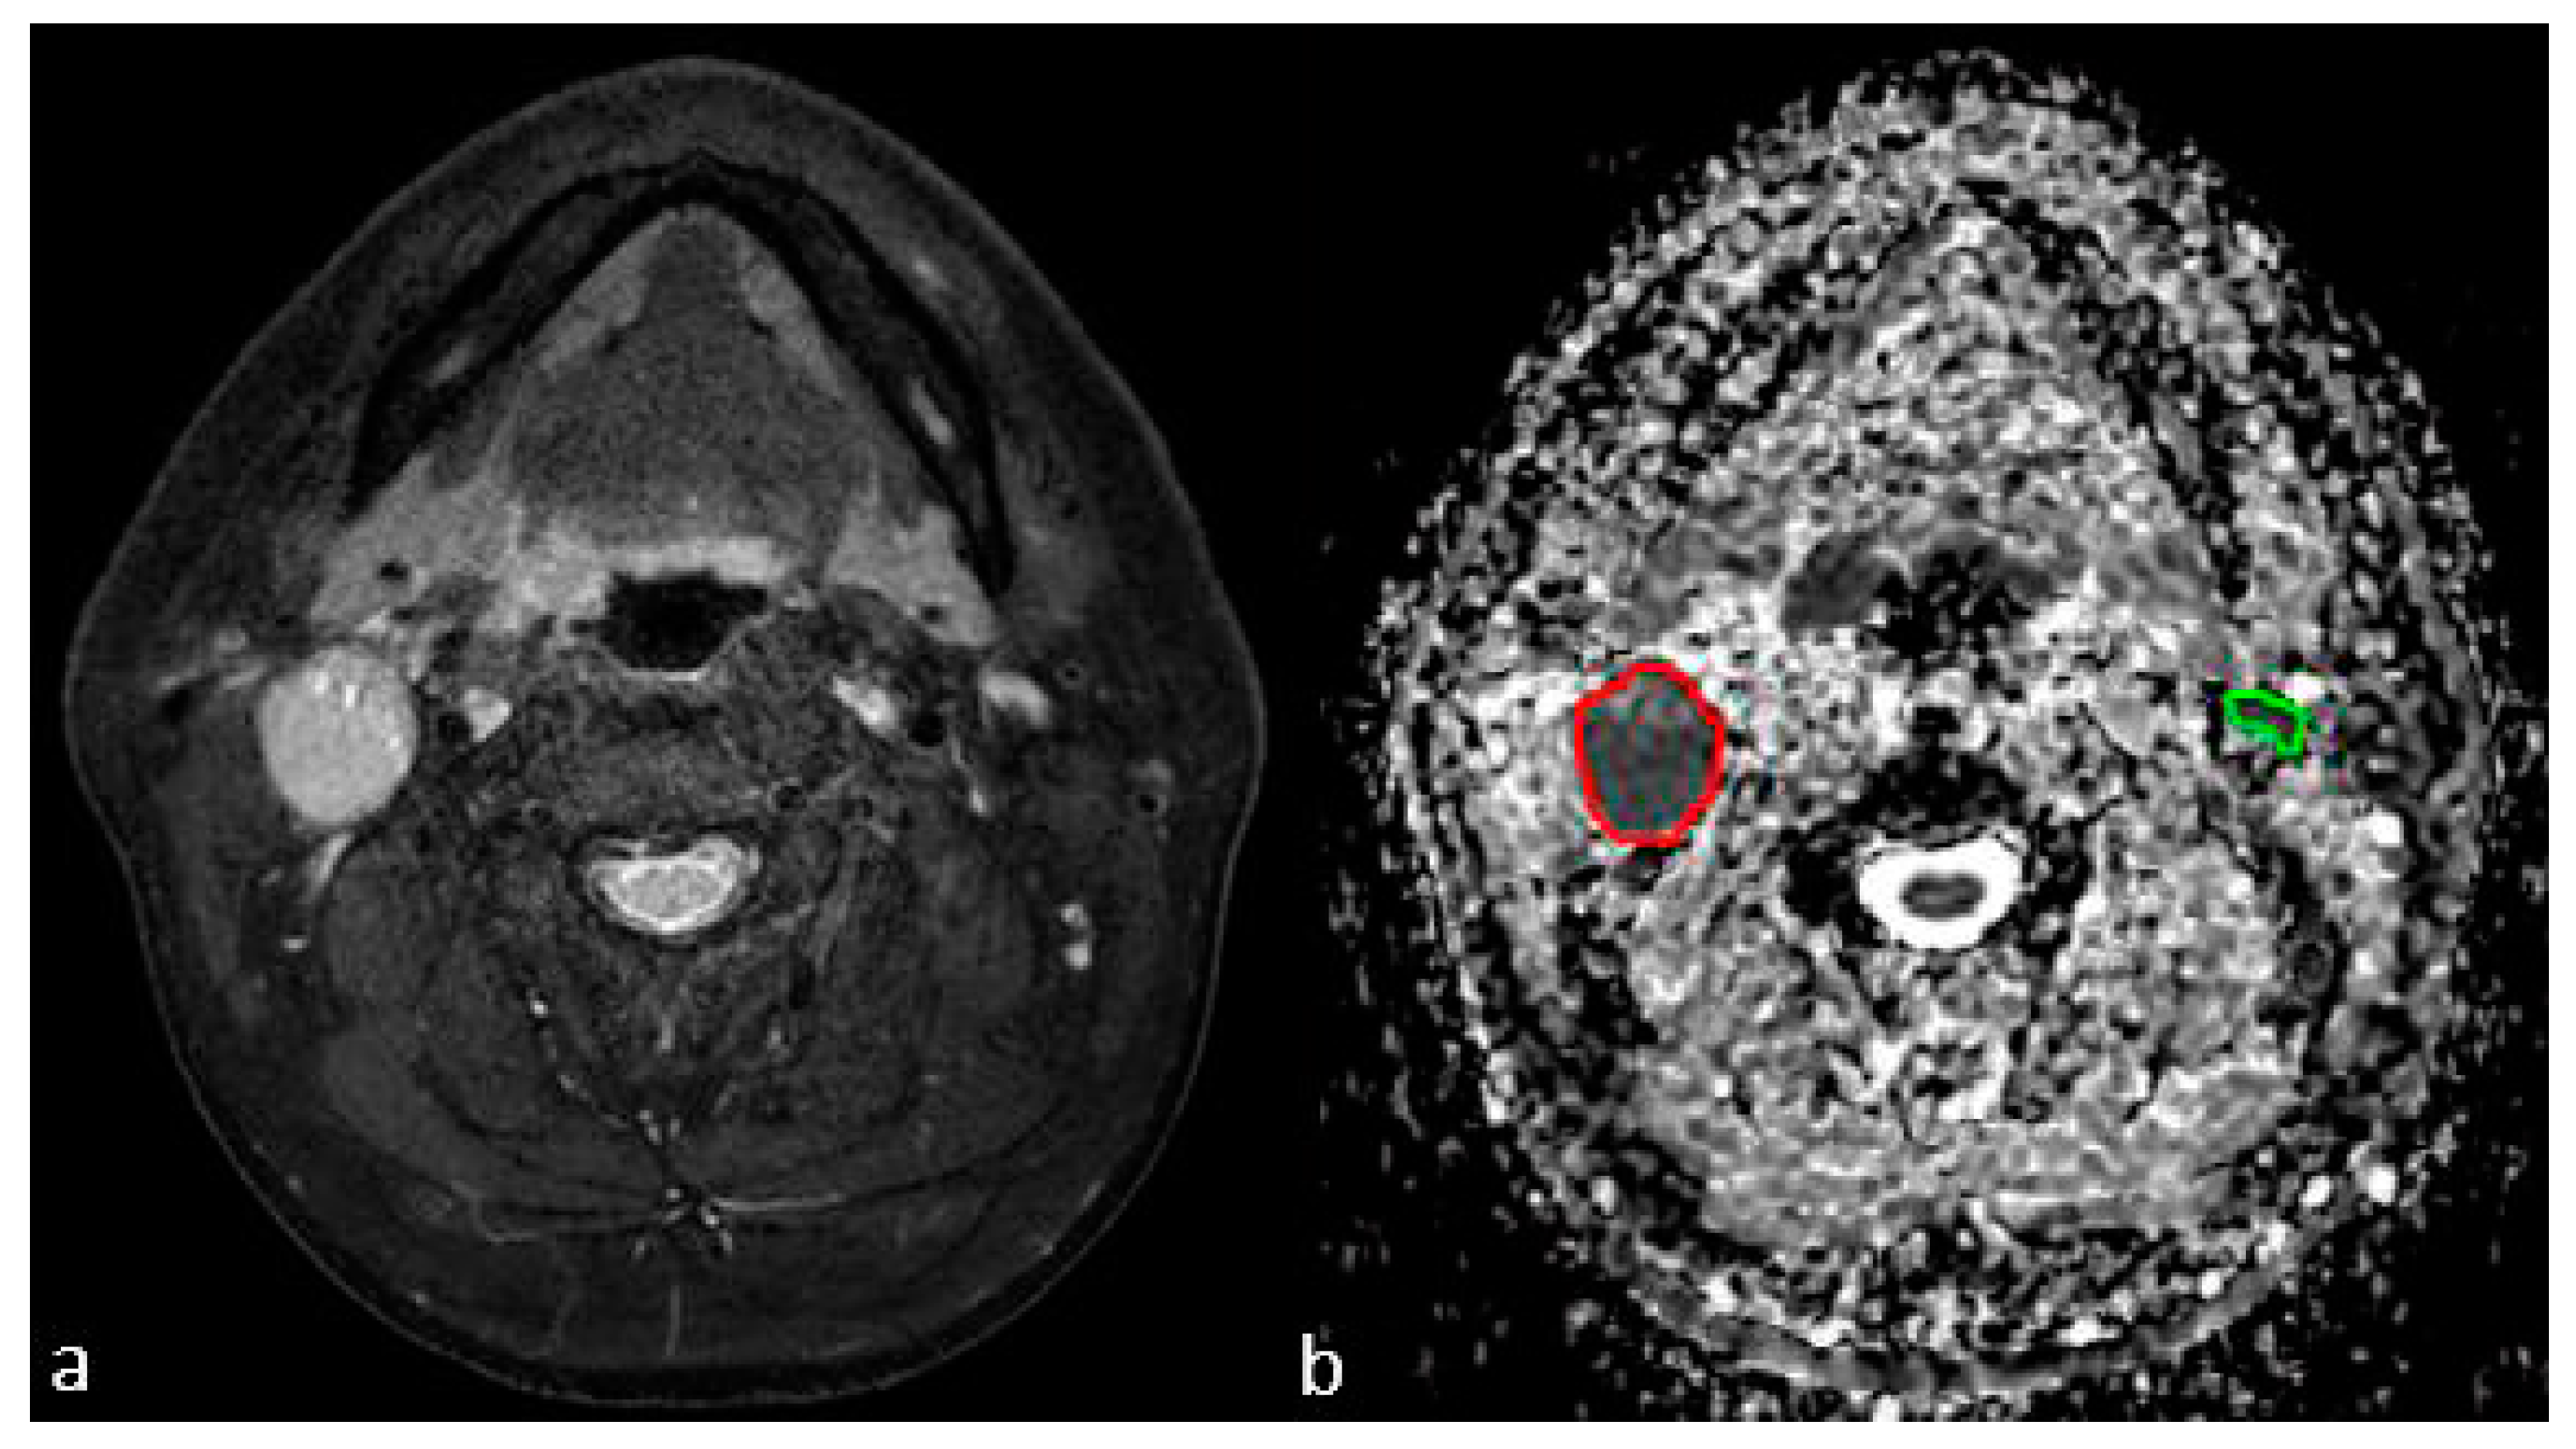

3.2. MRI Characteristics of LNs

3.3. ADC Texture Analysis